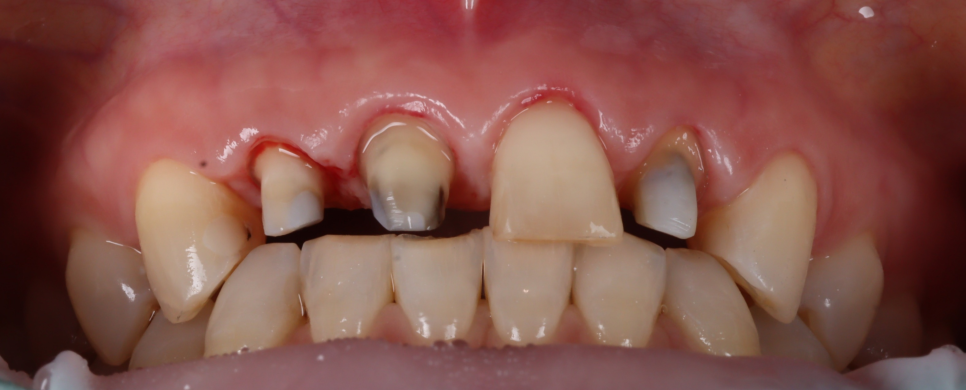

환자분께서는 웃을 때 잇몸이 많이 보이는 거미 스마일(Gummy Smile)을 개선하고 싶다고 하셨어요.

251105

잇몸이 치아를 많이 덮고 있어서 송곳니부터 송곳니까지 6개 치아를 잇몸 성형하기로 했습니다.

그 후 잇몸이 안정되면, 모델을 만들어서 앞니의 모양과 형태를 보고 더 상세한 계획을 세우기로 했어요.

잇몸성형 전, 후

251105 / 251117

잇몸이 안정된 뒤 기존 보철물은 전부 제거하고 치아 상태를 다시 확인했어요.